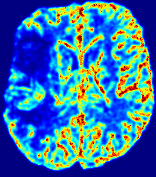

LesionRefer to captionRefer to captionRefer to captionRefer to captionRefer to captionRefer to caption𝐕rgbsubscript𝐕𝑟𝑔𝑏{\bf{V}}_{rgb}Refer to captionRefer to captionRefer to captionRefer to captionRefer to captionRefer to caption𝐕2subscriptnorm𝐕2{\|\bf{V}}\|_{2}Refer to captionRefer to captionRefer to captionRefer to captionRefer to captionRefer to captionRefer to caption3.53.53.52.82.82.82.12.12.11.41.41.40.70.70.70.00.00.0(mm/s)𝑚𝑚𝑠(mm/s)D𝐷DRefer to captionRefer to captionRefer to captionRefer to captionRefer to captionRefer to captionRefer to caption0.0200.0200.0200.0160.0160.0160.0120.0120.0120.0080.0080.0080.0040.0040.0040.0000.0000.000(mm2/s)𝑚superscript𝑚2𝑠(mm^{2}/s)Slice #1Slice #2Slice #3Slice #4Slice #5Slice #6

Figure 3: PIANO feature maps for one stroke patient, where the lesion is located in the left hemisphere. Top row: segmented stroke lesion region (white) on different slices, obtained from ISLES 2017. The corresponding slices for the PIANO feature maps are shown in the following rows.

For a better insight into an estimated velocity field 𝐕𝐕{\bf{V}} and diffusion field 𝐃𝐃{\bf{D}}, we compute the following maps: (1) 𝐕rgbsubscript𝐕𝑟𝑔𝑏{\bf{V}}_{rgb}: Color-coded orientation map of 𝐕=(Vx,Vy,Vz)T𝐕superscriptsuperscript𝑉𝑥superscript𝑉𝑦superscript𝑉𝑧𝑇{\bf{V}}=(V^{x},V^{y},V^{z})^{T}, obtained by normalizing 𝐕𝐕{\bf{V}} to unit length and mapping its 3 components to red, green, blue respectively; (2) 𝐕2subscriptnorm𝐕2\|{\bf{V}}\|_{2}: 222 norm of 𝐕𝐕{\bf{V}}; (3) D𝐷D: scalar field in Eq. 5.

Fig. 3 and Fig. 4 show the PIANO feature maps estimated from two ISLES 2017 patients: all are highly consistent with the lesion in both cases. Details of the blood flow trajectories are revealed in 𝐕rgbsubscript𝐕𝑟𝑔𝑏{\bf{V}}_{rgb} by the ridged patterns and the sharp changes of colors in the unaffected (right) hemisphere, while the flat patterns appearing within the lesion provide little directional information about the velocity and indicate low velocity magnitudes. Velocity magnitudes are more directly visualized via 𝐕2subscriptnorm𝐕2\|{\bf{V}}\|_{2}, from which one can easily locate the lesion where 𝐕2subscriptnorm𝐕2\|{\bf{V}}\|_{2} is low. D𝐷D also indicates lower diffusion values in the lesion, though with less contrast potentially due to the fact that it captures the accumulated effect of CA diffusion at the voxel-level.